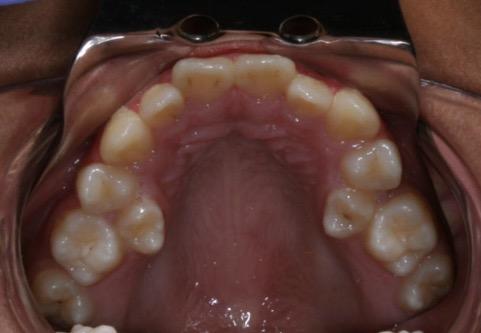

Στην ηλικία των 7 ετών, σύμφωνα με τις οδηγίες της Αμερικανικής Ορθοδοντικής Εταιρείας AAO (American Association of Orthodontics), καλόν θα είναι να εξετάζεται κλινικά αλλά και ακτινογραφικά η κατάσταση της μεικτής οδοντοφυίας του παιδιού για σκελετική ή οδοντική ασυμμετρία των γνάθων, για ελλείποντα δόντια ή δυνητικώς έγκλειστα ή για παρουσία οδοντωμάτων ή για έκτοπη ανατολή

Όταν υπάρχει γενετική έλλειψη μονίμων δοντιών αν επέμβουμε ορθοδοντικά σε μικρή ηλικία κλείνουμε τα κενά μικραίνοντας τα οδοντικά τόξα και έτσι το παιδί αποφεύγει μελλοντικές προσθέσεις (γέφυρες ή εμφυτεύματα).

Γενετικώς ελλείποντα δόντια (ο άνω αριστερός πλάγιος, ο άνω δεξιός 2ος προγόμφιος, οι κάτω δεύτεροι προγόμφιοι αμφοτερόπλευρα.)

Μετά το πέρας της ορθοδοντικής θεραπείας, (2η φωτογραφία), τα κενά που δημιουργήθηκαν

από την έλλειψη των μονίμων δοντιών μετά την φυσιολογική απόπτωση των νεογιλών δοντιών, έκλεισαν με ορθοδοντική παρέμβαση